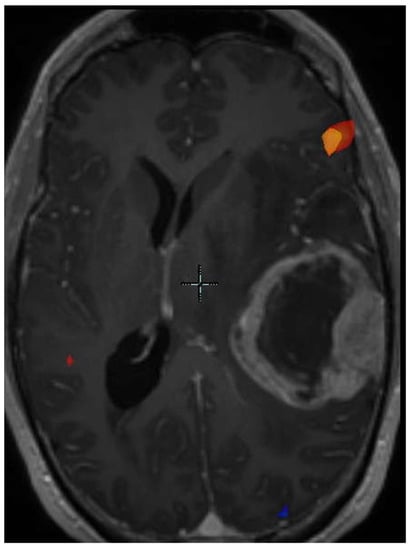

- Jones, K.K.; Maziero, D.; Ford, J.C.; Stoyanova, R.; Goryawala, M.; Diwanji, T.; Mellon, E.A. MRI-guided radiotherapy identifies early pseudoprogression of glioblastoma. Res. Sq. 2020. [Google Scholar] [CrossRef]